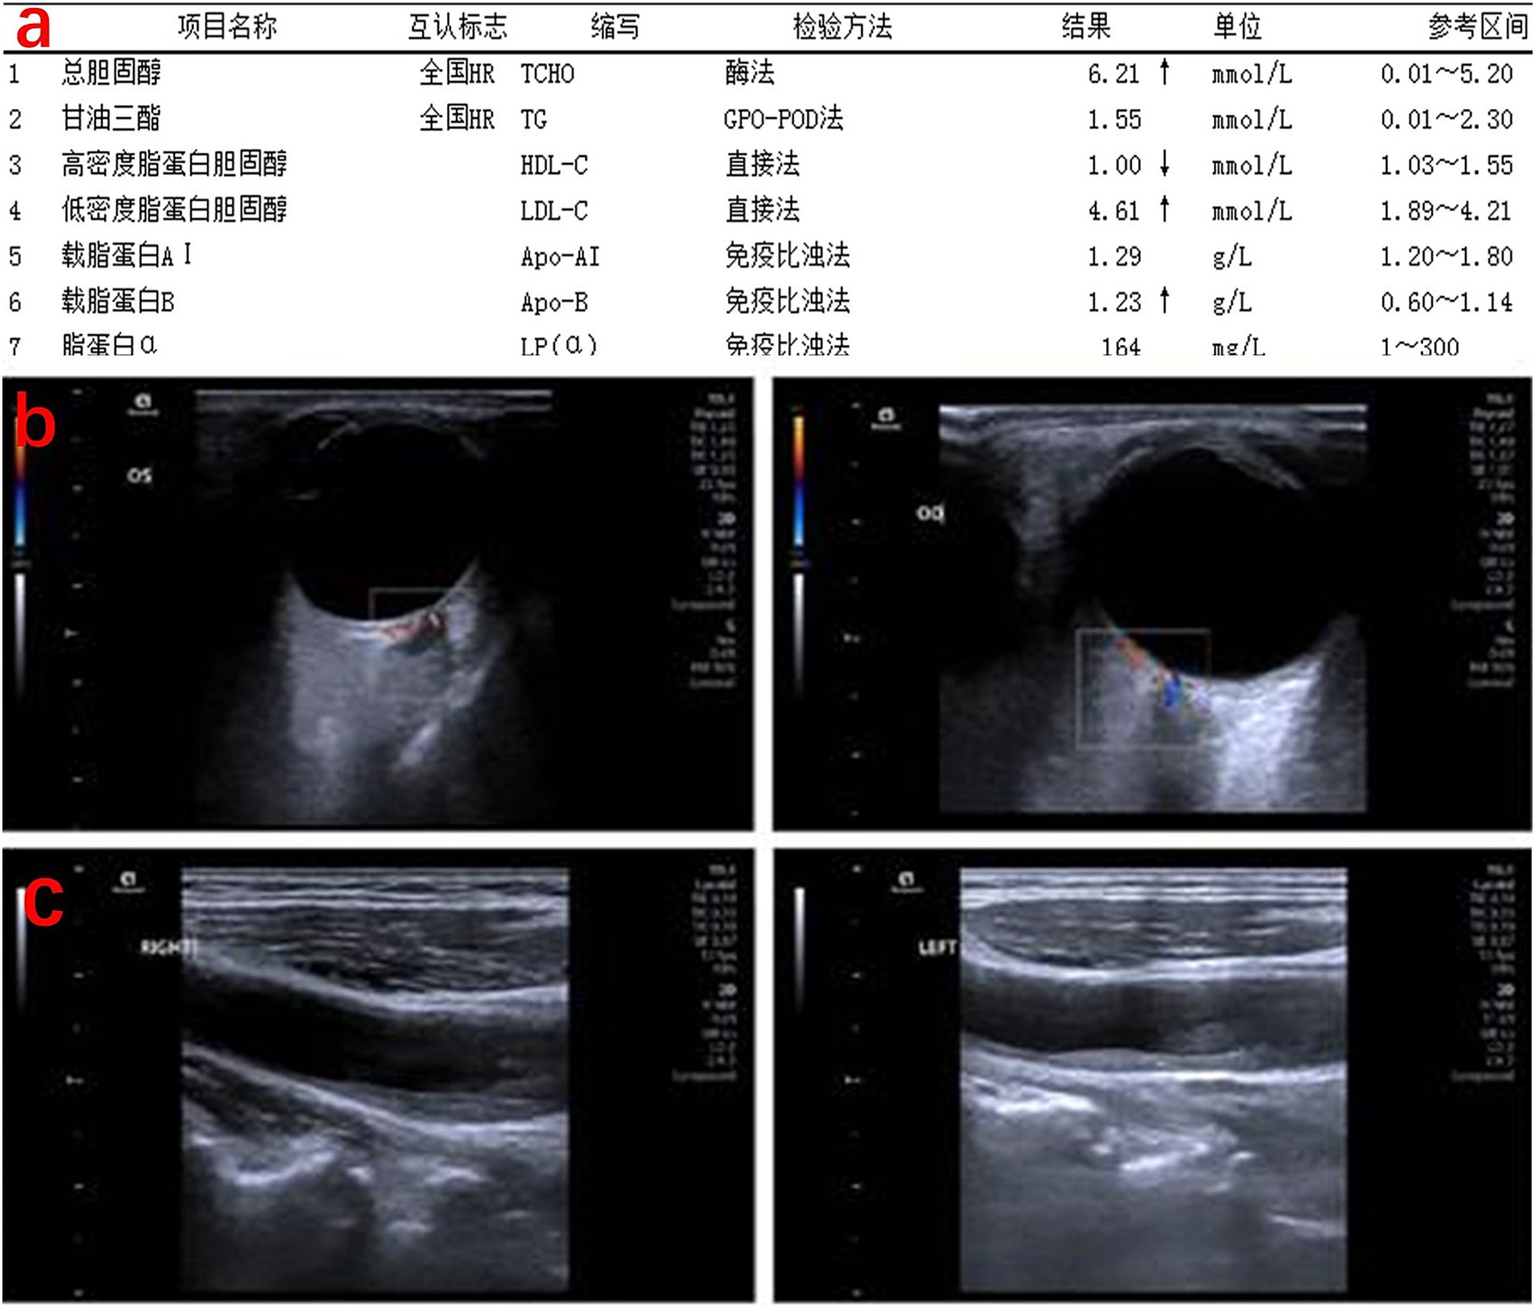

Fluorescein angiography (FFA) revealed normal arterial filling in the superior retina and delayed arterial filling in the inferior half of the right eye, with corresponding hypofluorescence in the inferior background (Figure 3a). In the late phase, macular capillary dropout and mild fluorescein pooling were observed (Figure 3b). The left eye exhibited media opacity and, during the venous phase, patchy subretinal hemorrhage in the inferonasal quadrant with corresponding hypofluorescence (Figure 3c), along with subtle microaneurysm leakage and neovascular leakage (Figure 3d). Based on these findings, FFA confirmed branch retinal artery occlusion (BRAO) in the right eye and branch retinal vein occlusion (BRVO) in the left eye. Laboratory tests revealed significantly elevated total cholesterol (Figure 4a). Color Doppler ultrasound indicated reduced flow in the right posterior ciliary artery (Figure 4b), and carotid ultrasound showed bilateral atherosclerosis with plaque formation (Figure 4c). The patient received posterior sub-Tenon injections of dexamethasone (2.5 mg/0.5 mL) and anisodamine (5 mg/1 mL) once daily for five consecutive days. Meantime, this patient received superficial temporal artery injections of compound anisodine (2 mL per day) administered once daily for 7 days. Intravenous vinpocetine (20 mg diluted in 500 mL of 0.9% normal saline) was given via slow infusion once daily for 7 days to promote vasodilation. After treatment, fundus photography of the right eye showed improvement in cotton-wool spots, and OCT demonstrated a reduction in macular edema with improved morphology, though the retinal layers remained poorly defined (Supplementary Figures 1a,b). The left eye underwent retinal laser photocoagulation for ischemic BRVO, followed later by cataract surgery. Fundus photography showed laser scars surrounding a ring-shaped exudative lesion, with hemorrhages along the major vessels below the optic disc and vessel narrowing with peripheral hemorrhages in the inferonasal mid-periphery (Supplementary Figure 1c). OCT of the left macula remained unremarkable (Supplementary Figure 1d). The right eye was managed with vasodilators and medications to relieve vascular spasm and reduce intraocular pressure (not anti-glaucoma therapy). Upon discharge, the patient’s BCVA improved to 1.0 in the left eye and 0.8 in the right eye. He was advised to continue antihypertensive treatment and return for regular follow-up.

Figure 4

Lipid profile and vascular status of the patient. (a) Lipid profile: total cholesterol significantly elevated. (b) Posterior ocular vessel ultrasound: the right retinal central artery shows significantly reduced flow and velocity, with occlusion not ruled out. Reduced flow velocity in the right nasal ciliary posterior short artery. (c) Carotid ultrasound: bilateral carotid artery walls are irregular, with hypoechoic, hyperechoic, and mixed echogenic plaques visible in the common carotid artery, bifurcation, and the origin of the internal carotid artery. Blood flow filling defects are observed at the plaque sites.